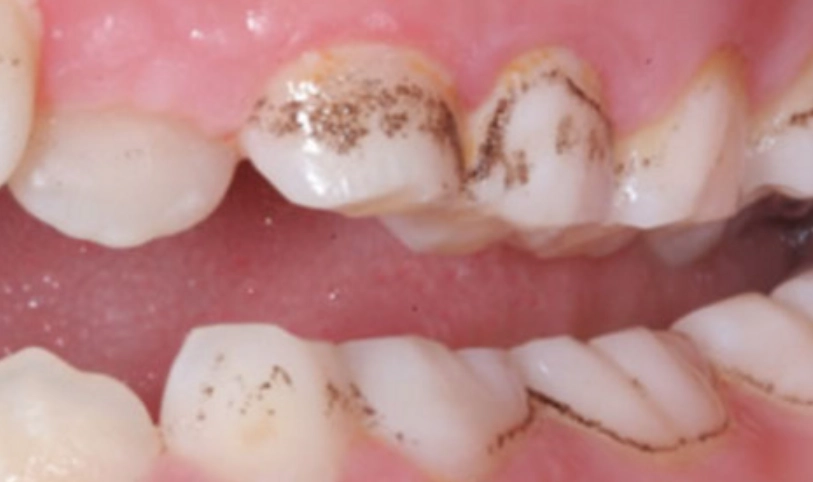

最麻煩的一點是,如果沒有及時清除,牙菌斑裡的細菌會分解食物中的糖分,產生酸性物質。這些酸會腐蝕牙齒琺瑯質,蛀牙就來了。同時,牙菌斑如果堆積在牙齦邊緣,會刺激牙齦發炎,紅腫流血,這就是牙齦炎。再放任下去,發炎往牙根深處走,破壞牙周組織,變成牙周病,牙齒就可能開始搖動。

細菌靠糖分生存。減少高頻率的糖分攝取,比單純減少總糖量更重要。頻繁喝含糖飲料、吃零食,等於不斷餵養牙菌斑裡的細菌,讓口腔環境長期處於酸性狀態。

吃完東西後,如果無法立刻刷牙,可以喝點白開水,或咀嚼無糖口香糖(特別是含木糖醇的),刺激唾液分泌,唾液有天然的緩衝和清潔作用。